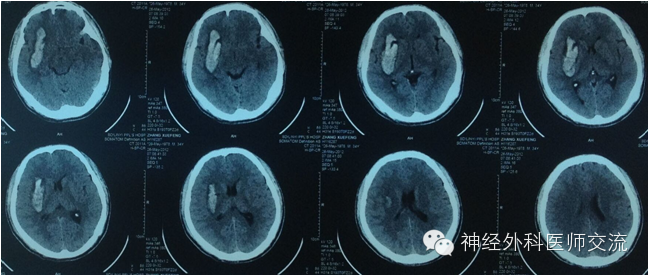

①对于稳定性脑出血,在穿刺术实施2~4 h后可行液化术。

②尿激酶液的配制:尿激酶2~10万u~10万u溶于NS 3~4 ml中。

③用5 ml注射器抽取尿激酶溶液3~4ml,旋转三通开关开通侧臂,消毒三通阀的侧臂肝素帽,穿刺三通阀的侧臂肝素帽,沿三通阀的侧臂将液化剂——尿激酶溶液注入血肿腔内。

④关闭三通阀2~4小时后,打开三通阀开关,行引流术;每日注入液化剂(尿激酶液)1~2次。若液化后引流不畅,可挤捏引流导管颅外段。

体会:引流不畅的原因——出血已被彻底清除、引流导管位置不合适、血肿液化不理想、颅内压相对偏低、引流器的滴壶放置位置偏高、引流导管被堵塞或引流导管及连接管折叠等因素。